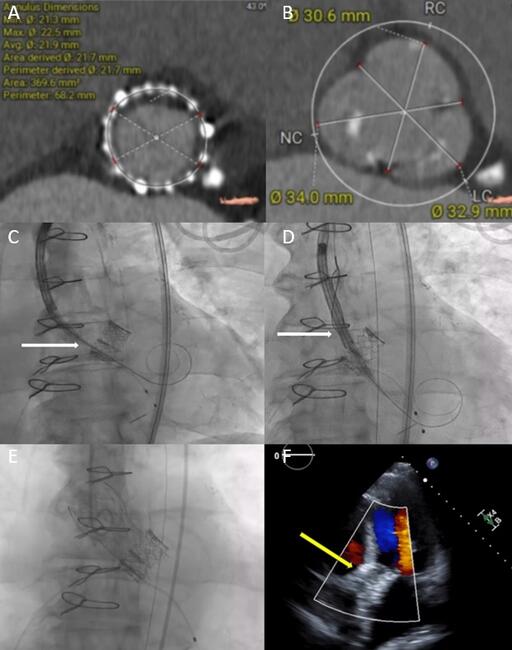

An 82-year-old man with a prior history of transcatheter aortic valve replacement (TAVR) with a 23-mm balloon-expandable transcatheter heart valve (THV) presented with bioprosthetic stenosis. Preoperative computed tomography revealed an underexpanded THV (Figure, A) with large sinuses with no risk for coronary obstruction (Figure, B). Hence, we decided to use a 26-mm self-expandable THV (Evolut FX 26 mm, Medtronic) to optimize hemodynamics for redo-TAVR.

The THV was crossed and a pre-shaped stiff wire (Confida, Medtronic) was inserted into the left ventricle apex. We were unable to advance the self-expandable prosthesis past the frame of the initial THV despite multiple attempts due to bias towards the greater curvature (Figure, C; Video 1). Next, we advanced a 25-mm Amplatz Goose Neck snare catheter (Medtronic) around the self-expandable THV and facilitated entry through the THV by pulling towards the lesser curvature. This snare technique centralized entry of the THV, and we were then able to perform successful redo-TAVR (Figure, E & F; Video 2)